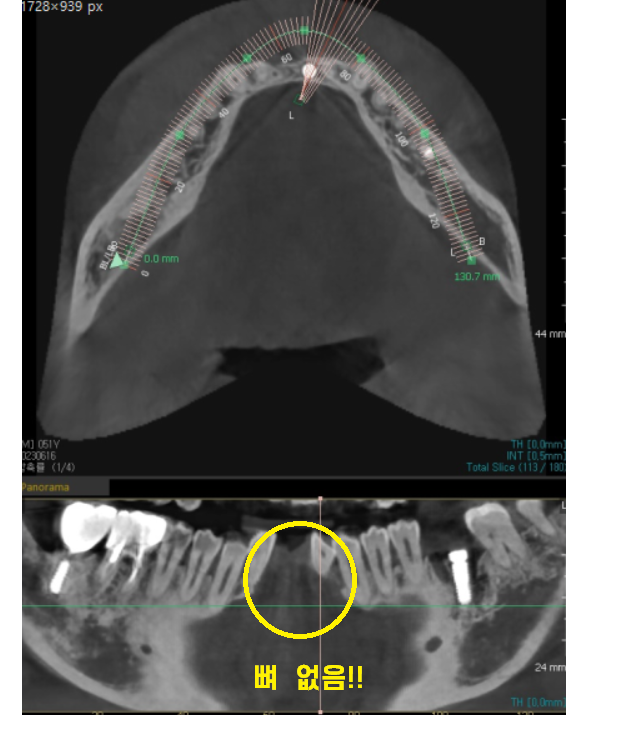

23.06.16

ct를 보시면 임플란트가 뼈 폭에

기가막히게 딱 ! 맞아 떨어집니다!

두개의 임플란트를 못심을정도로

뼈가 없었지만

일체형 임플란트를 통해

아래 앞니 임플란트 해결했습니다!!